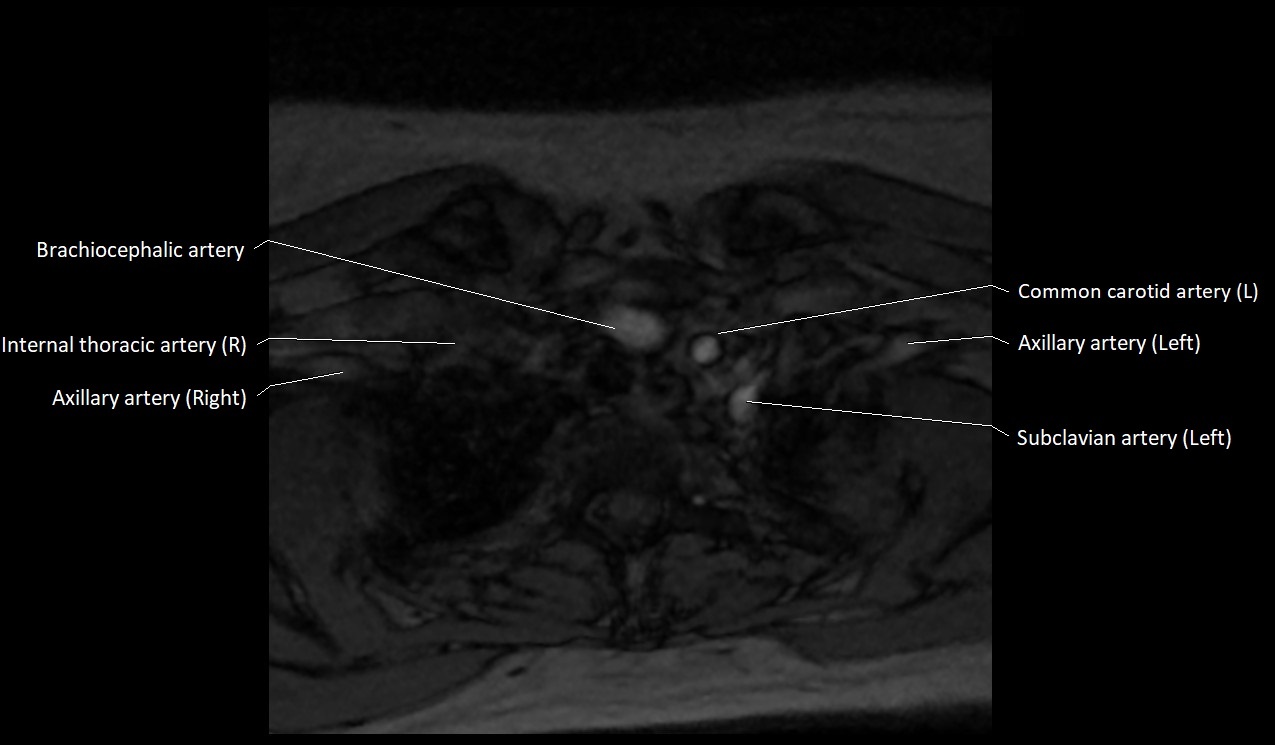

MRI images

image